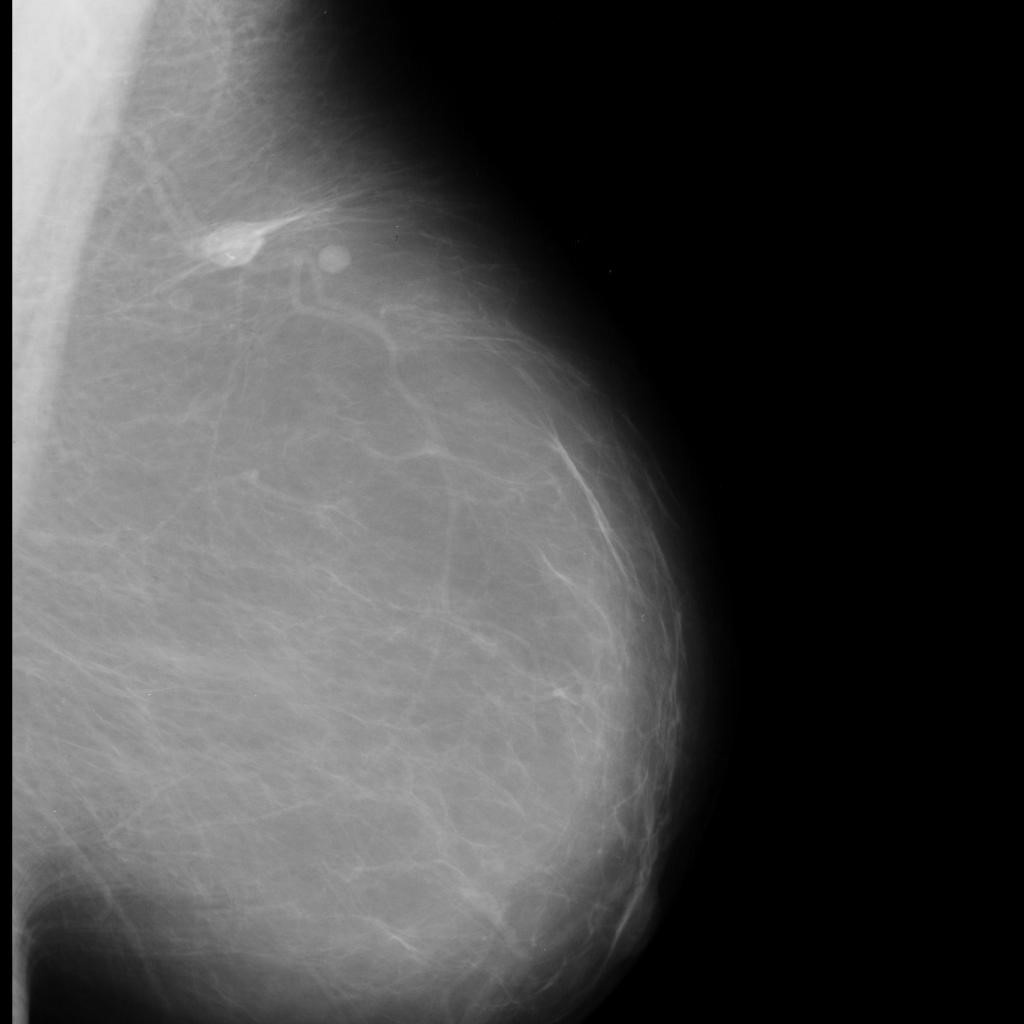

benign